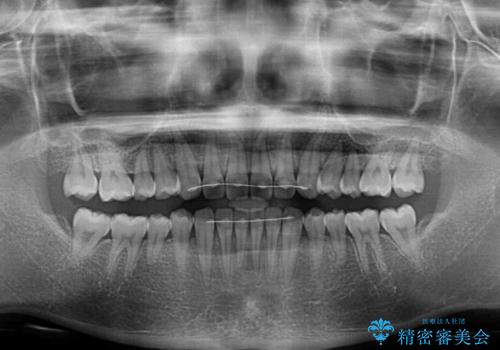

- 上の前歯の隙間を気にして来院された患者様です。

インビザラインにより、隙間を閉じながら、隙間の原因であるディープバイトを改善していくこととしました。

下顎の歯列が強く上顎に咬みこむことで隙間ができてしまうため、マウスピースの保定装置では後戻りのリスクが高くなってしまいます。

そのため、上下ともに前歯の裏側を細いワイヤーで固定し、その上から保定装置のマウスピースを使用していただくこととしました。